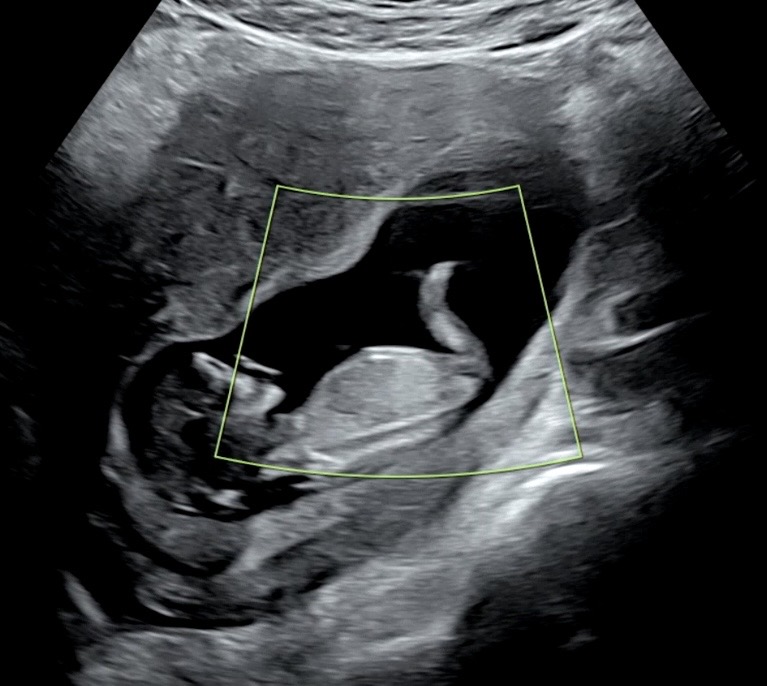

애기가 구석에 있어서 잘 안보이기는 한데 각도법 고수님들 12주인데 딸, 아들 각도법 좀 봐주세요~